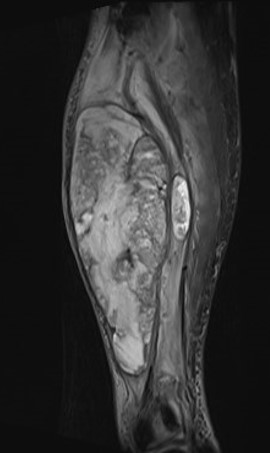

MRI

Pleomorphic rhabdomyosarcoma adult